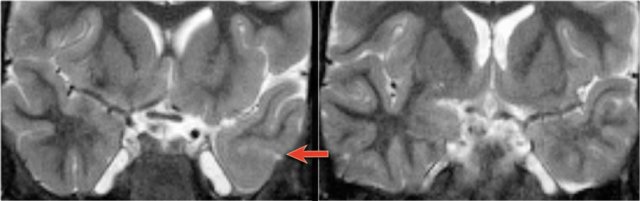

First study the images and then continue reading.

This patient has a bilateral schizencephaly.

There is an open-lip type on the right and a closed-lip type on the left (red arrow).

Notice the track of grey matter in the left hemisphere on the axial image.

The differential diagnosis of schizencaphaly is porencephaly, which is also a cleft, but it is not lined by grey matter.